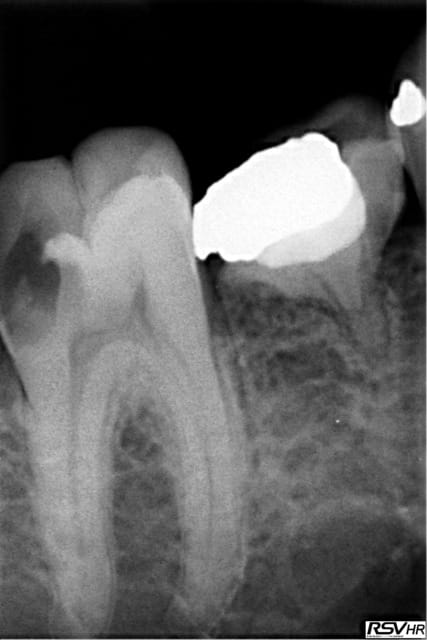

Pour abonder dans le sens qu'il ne faut pas couronner dans tous les cas, voici un cas fait il y a un an.

Les facteurs qui m'ont amené à prendre la décision de faire une endocouronne (proche d'un onlay en vérité) :

- 3 parois solides, la dernière pas trop fine.

- limites toutes supragingivales

- occlusion favorable (pas de photos de l'antagoniste je n'y ai pas pensé)

- patient réceptif

- grande profondeur de la chambre pulpaire (pas très visible sur les photos verticales)

Je n'en fais pas souvent mais quand j'en fait c’est que j'ai confiance. Faire une couronne classique ? Sur ce cas rien que de préparer les limites périphériques et on se retrouve avec une dent à raz la gencive, avec obligation de faire un (ou plusieurs) tenons longs pour une bonne rétention, générateur de fracture radiculaire....

Couronne Emax, collée au Multilink Automix

PS : avant toute remarque, non la patiente ne veut pas que je touche à sa dent de lait résiduelle ;o)